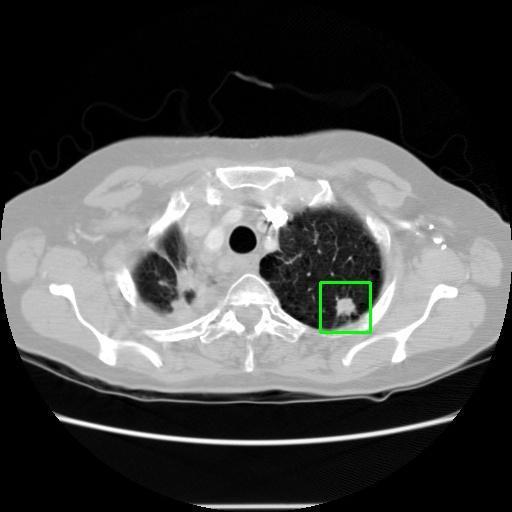

We developed an AI-based system using deep learning models for analyzing lung CT scans to detect and classify pulmonary nodules. We chose the YOLOv11 architecture for its enhanced object detection capability and adapted it specifically for medical imaging, incorporating pixel-level precision and severity classification.

Classification into three severity levels with colored bounding boxes.

Designed a severity classification system that categorizes nodules into null, moderate, and severe using colored bounding boxes, assisting in rapid clinical decision-making.